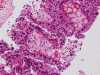

On FNA with Pap stain, clusters of cells with a papillary structure are present (Panel A). A delicate fibrovascular core can be seen at the center (arrow in Panel B). In higher magnification, two population of cells are present. While one of the population appears as solid sheets of polygonal epithelial cells with increased nuclear cytoplasmic ratio and distinct cell border (arrow head in Panel C), there are also many cells with distinctly foamy cytoplasm, lower nuclear cytoplasmic ratio and bland nuclei, and indistinct cell border (arrow head in Panel C). The foamy cells are most consistent with foamy macrophages. A distinct nucleoli is present in the epithelial cells (Panel D). The papillary morphology is well demonstrated in the cell block (Panel E, F, and G). Characteristically, the papillary structures are formed by a central core of foamy macrophages and covered by a epithelial cells. The epithelial cells but not the foamy macrophages are immunoreactive for CD10, AMACR, and CK7 (Panel H, I, and J).

| DIAGNOSIS: Papillary renal cell carcinoma. |